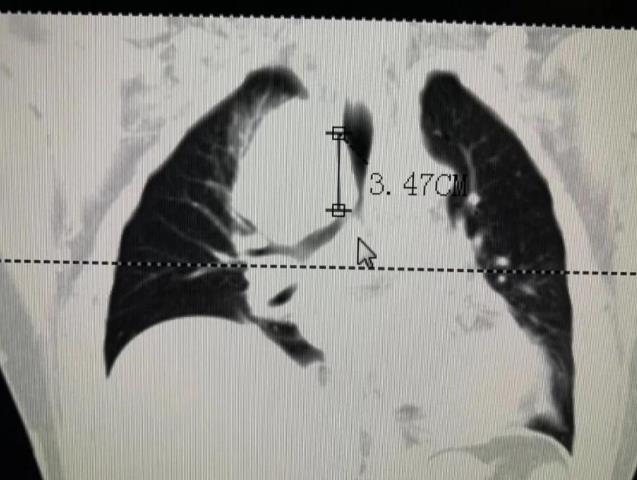

入院進行相關的檢查,肺部CT檢查結果顯示:由于縱隔上的腫瘤壓迫患者氣管導致狹窄呼吸困難,找到張先生病灶原因后,牛院長帶領醫療團隊經過多次閱片、討論,一致認為目前最先要解決的是困擾張大叔的呼吸問題,時間拖得越久就容易出現呼吸、心跳驟停的可能。

2020年4月8日,牛院長團隊通過DSA+CT技術不僅快速準確找到狹窄的支氣管,還更為清楚地看到腫瘤及其他周圍組織的關系。在氣管鏡下,牛院長熟練進行著進導絲、送置入器、釋放支架等等步驟;隨后在微波射頻消融設備下,將穿刺針刺入縱膈上的腫瘤部位,利用射頻發熱原理使腫瘤部位壞死。歷時一個半小時手術順利結束。